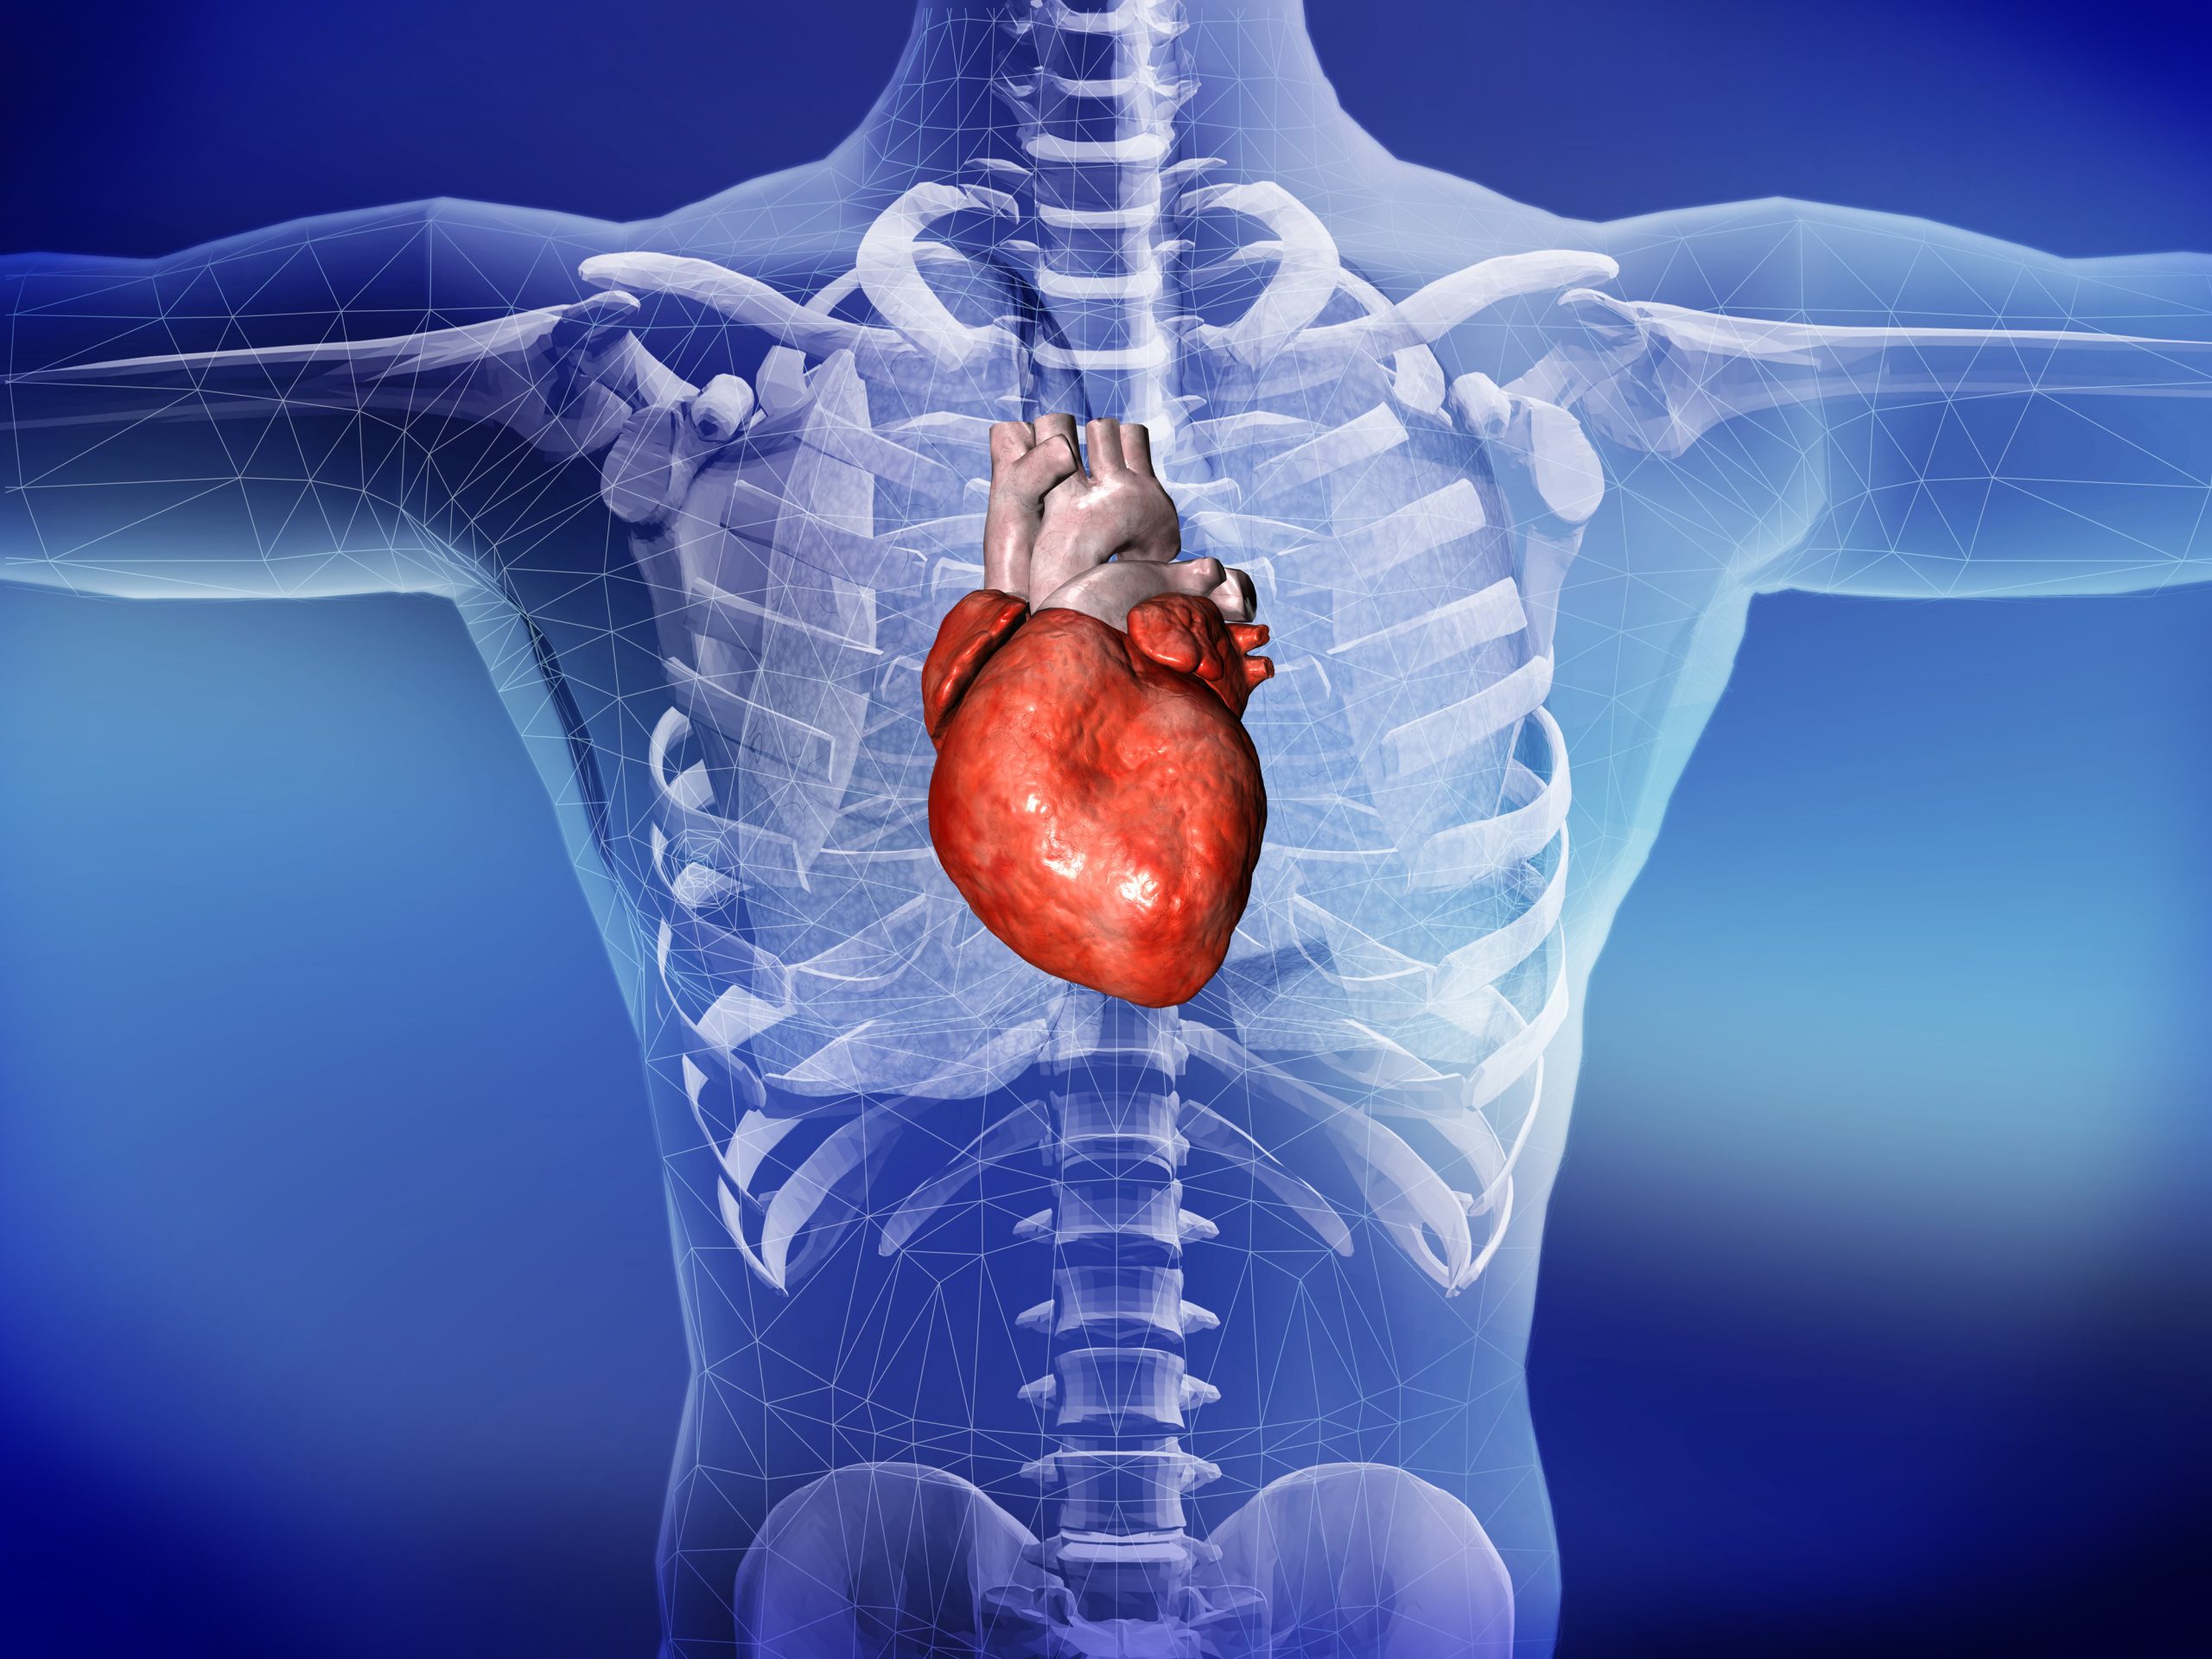

Анатомия Сердца: Расположение и Функции